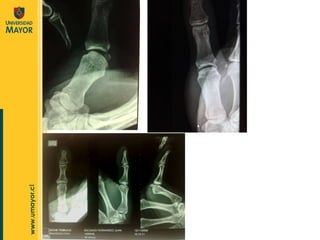

Imperativo Confirma el diagnóstico  y la variedad de luxación. Estudio de Imágenes  Luxaciones Establece si hay  fracturas asociadas. Importancia terapéutica y legal .  La radiografía simple es de elección.

Estudio de Imágenes  Rx. Siempre a dos planos  e inclusive axial(es). TAC RNM Luxaciones